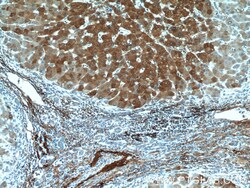

15833-1-AP IHC

Method: Other validation